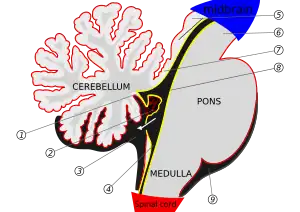

2. : Plexus choroïdes

3. : Grande citerne du cervelet

4. : Canal central

5. : Colliculi

6. : Pédoncule cérébral

7. : Anterior medullary

8. : Limite épendymaire du ventricule

9. : Citerne pontique de la cavité sous-arachnoïdienne

Anatomiquement, le pont est la portion du métencéphale située en position caudale par rapport au mésencéphale, crânial par rapport à la moelle allongée et ventral par rapport au cervelet. Chez l'humain en position debout, cela le place donc au-dessus de la moelle allongée dont il est séparé par un sillon marqué sur la face antérieur du tronc : le sillon bulbo-pontique. La frontière supérieure du pont avec le mésencéphale est marquée par le sillon ponto-pédonculaire.

Chez l'adulte humain, le pont mesure entre 25 et 27 mm de haut et environ 30 mm de long. Il apparaît comme un renflement (d'où son nom de protubérance) de la face antérieure du tronc cérébral dont la face antérieure est creusée, en son centre, par une gouttière dite sillon basilaire où circule le tronc basilaire. La face postérieure du pont constitue le triangle supérieur du plancher du quatrième ventricule et est bosselée par les noyaux des nerfs crâniens.

Contrairement au reste de la substance blanche du tronc cérébral, la protubérance annulaire est constituée en majorité de fibres nerveuses transverses qui la parcourent de gauche à droite ou de droite à gauche et non de haut en bas. Une proportion importante de cette substance blanche constitue les fibres ponto-cérébelleuses qui forment de part et d'autre les deux pédoncules cérébelleux moyens vers le cervelet. Les neurones d'où sont issues ces fibres, situés dans la partie ventrale du pont participent au faisceau cortico-pontin de la voie extra-pyramidale qui est impliqué dans la coordination et le contrôle moteurs.